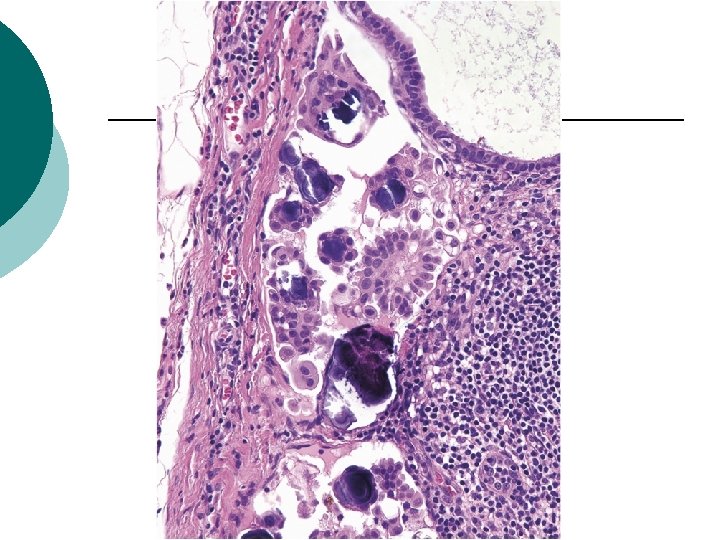

Individual cells, clusters of cells, and simple papillae

Individual Cells, Clusters of Cells, and Simple Papillae ¡ ¡ ¡ The most common pattern of LNI by S-LMP(28/31) 5 of these patients had stromal microinvasion and 4 had micropapillary architecture in the primary ovarian tumor. 16 patients with this pattern of LNI had noninvasive peritoneal implants, whereas 6 had invasive implants and 2 had implants that were indeterminate for invasion. Follow-up information : 2 DOD at 8 and 74 months, 3 AWD (11, 61, and 230 months), 15 NED, and 8 with no available follow-up data Disease-free survival versus LNI without this pattern : 75% and 50%, respectively (P=0. 42).